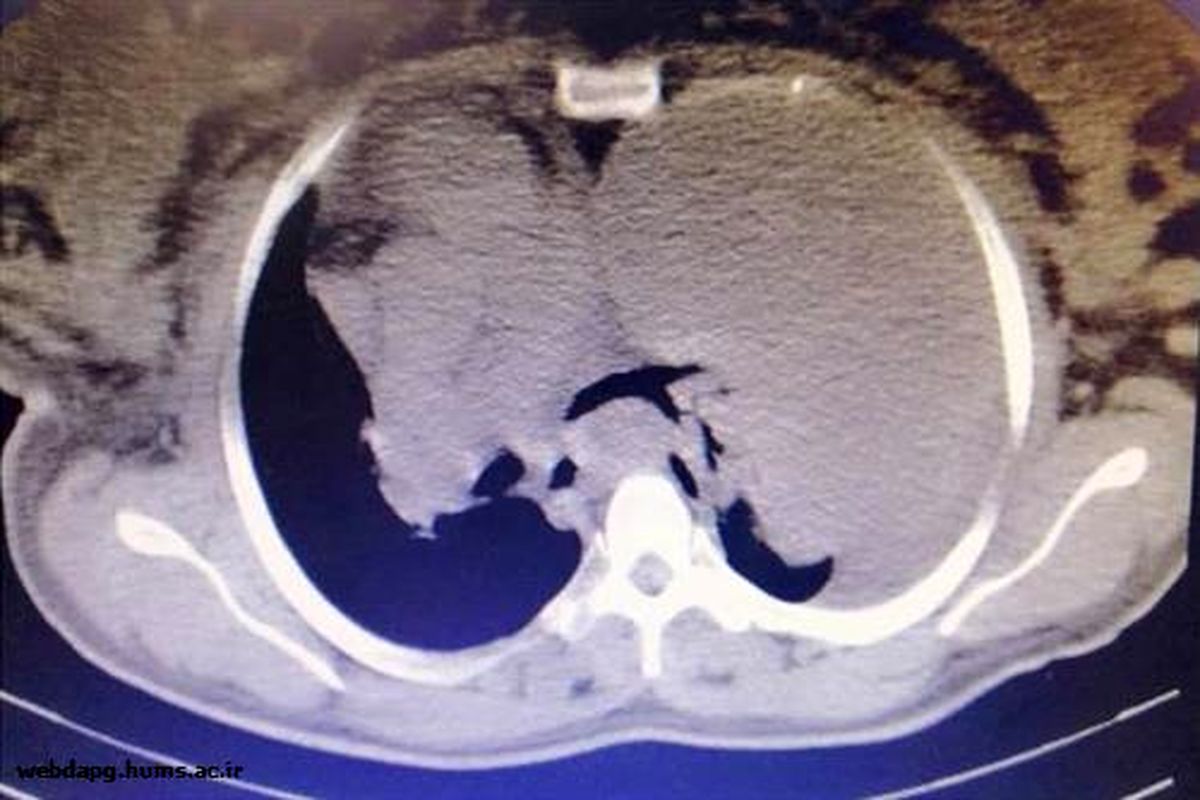

به گزارش خبرگزاری موج هرمزگان، وحید دهستان فوق تخصص ریه با بیان وضعیت بیمار گفت: بیمار یک خانم  ۳۳ ساله و حدود ۳۴ هفته بارداری با علائم تنگی نفس، سرفه و درد در قفسه سینه به بیمارستان شهید محمدی مراجعه کرد، که در معاینات بالینی و بررسی نخست از جمله سونوگرافی ریه احتمال وجود تومور ریه نیز مطرح شد و جهت اقدامات تکمیلی، عکس از قفسه سینه و سی تی اسکن انجام که پس از نمونه برداری از طریق پوست وجود تومور محرز شد.

فوق تخصص جراحی توراکس بیمارستان شهید محمدی بندرعباس با اشاره به اینکه این عمل جراحی جزو اعمال جراحی نادر در استان است گفت: این عمل با توجه به حساسیت بالا و رشد زیاد تومور در ریه به حدی که آئورت و قلب را به طرف مقابل فشار داده بود، با تلاش تیم پزشکی با موفقیت صورت گرفت.

سید حسام الدین بنی هاشمی افزود: با توجه به اندازه تومور و اینکه تومور از داخل به دیافراگم نیز چسبیده بود در نهایت با همکاری تیم بیهوشی و اتاق عمل، توموری به اندازه ۲ کیلوگرم از ریه سمت چپ بیمار خارج گردید؛ و نمونه جهت بررسی به بخش پاتولوژی ارسال شد.